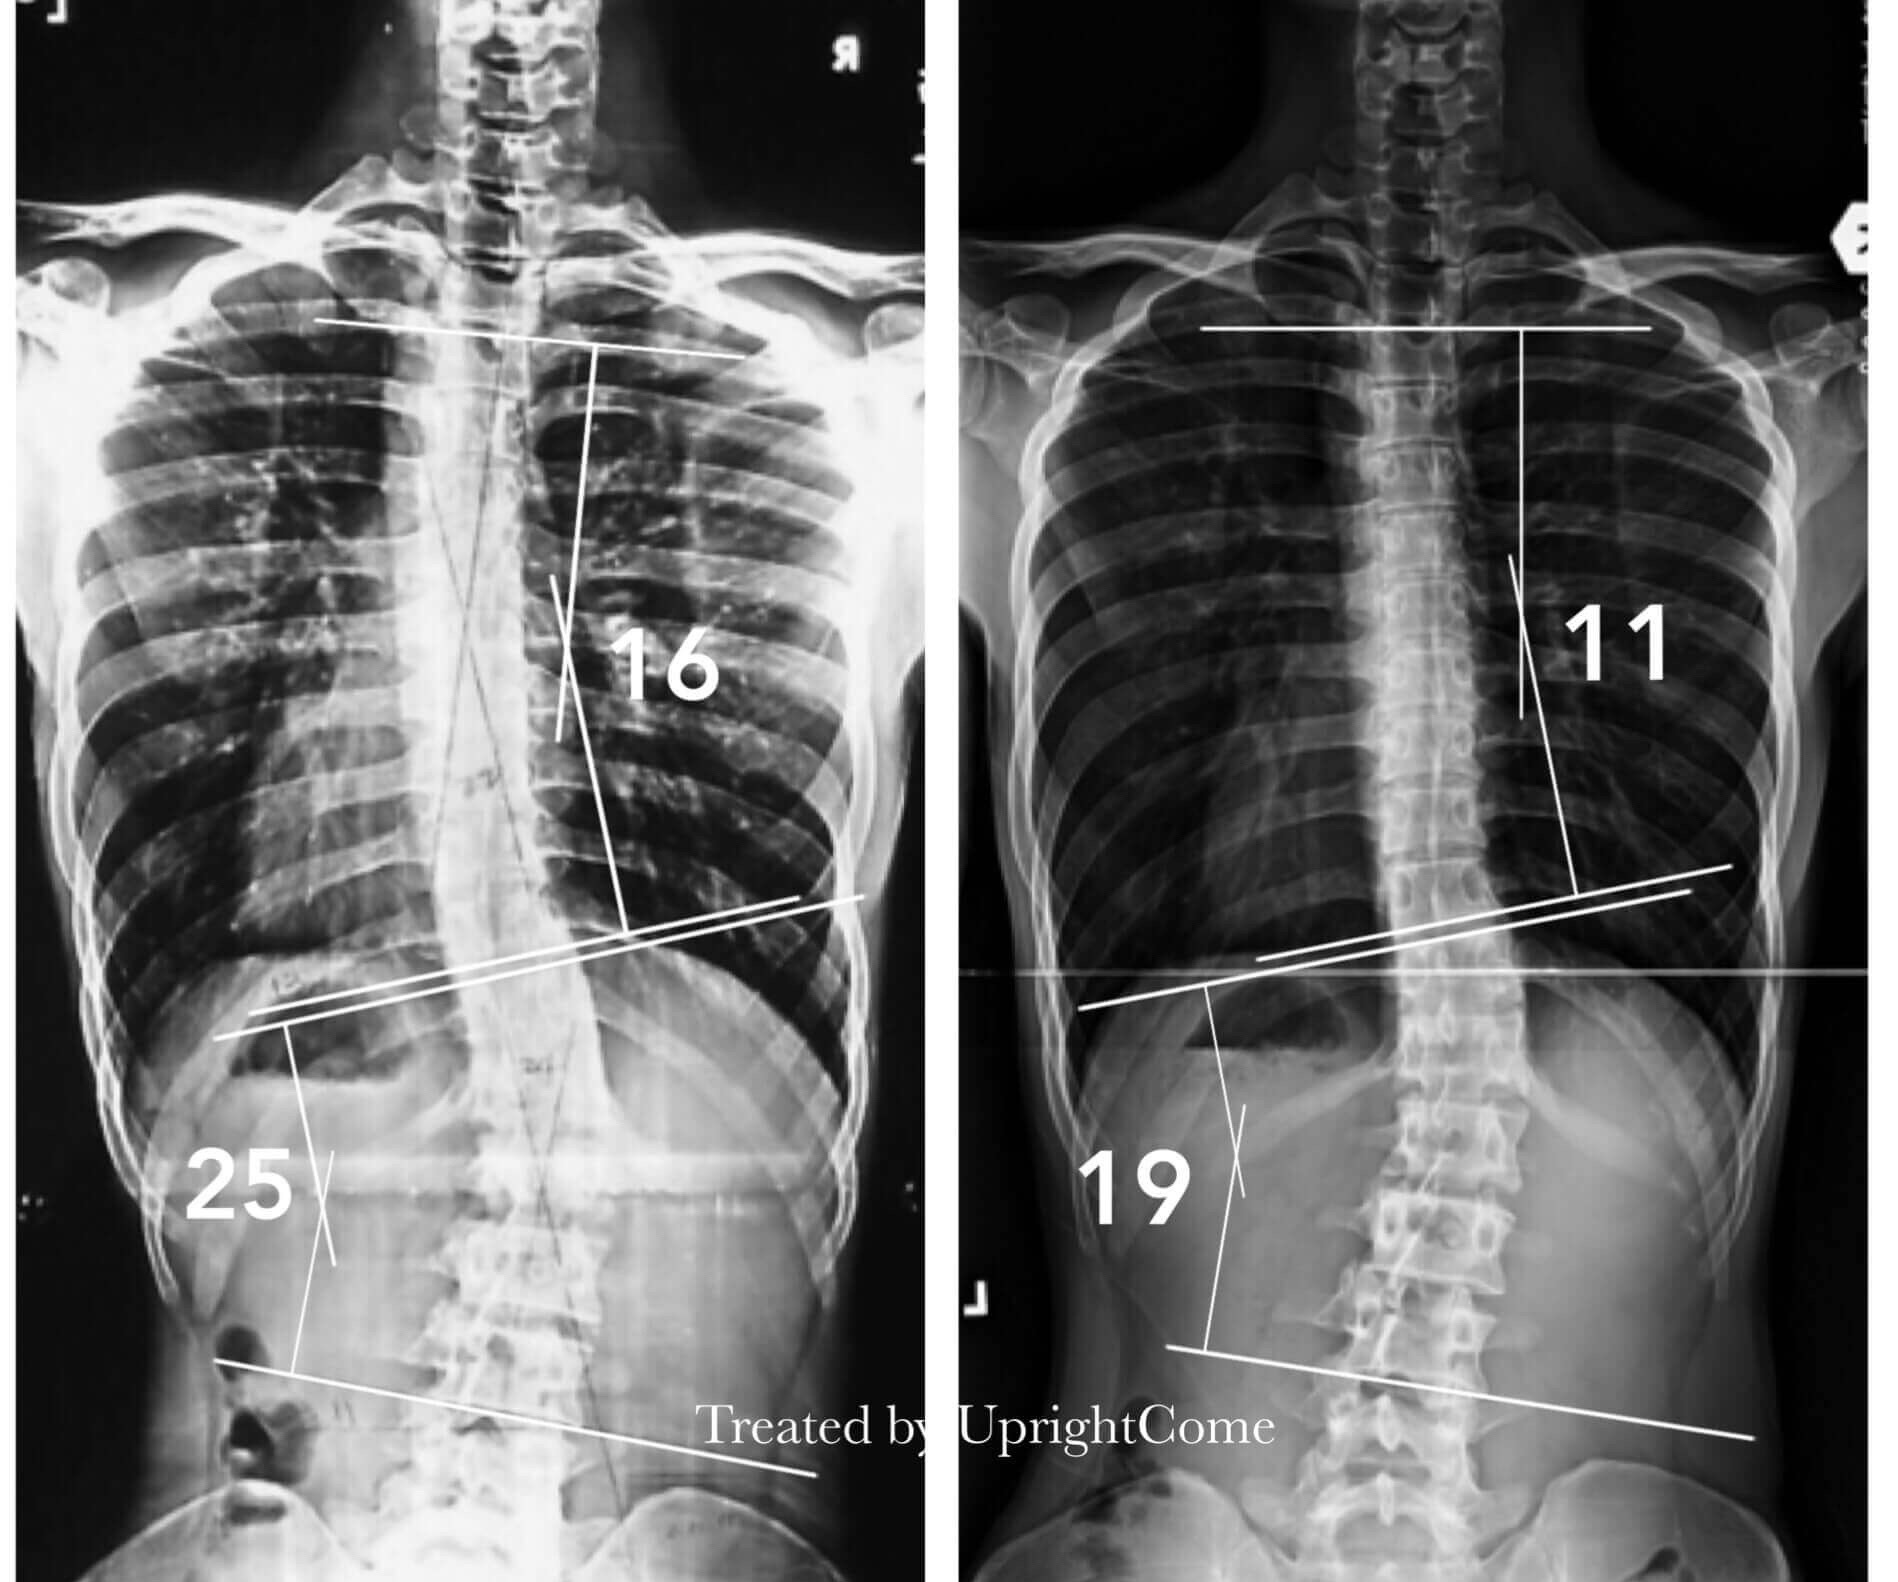

案例 24,22 歲,25 度側彎

![脊椎側彎患者經過側彎矯正治療後,胸椎角度由16度減少到11度,腰椎角度由25度減少到19度。]()